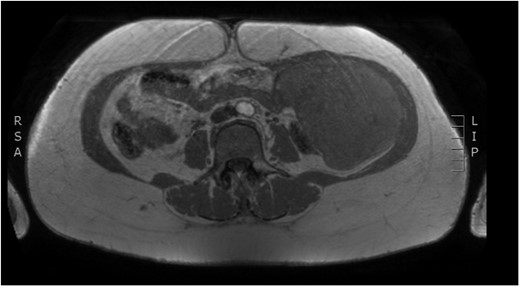

Physical examination revealed a painless, mobile parietal mass on the left anterior abdominal wall, more prominent during cough, of ~13 cm in diameter, with smooth contour and without skin involvement. Laboratory examination including cancer marks showed results within normal limits; hydatid serology (IgG antibodies) was also negative. As ultrasonography results were inconclusive, further imaging with magnetic resonance imaging (MRI) revealed a sizable cystic mass measuring 10 × 13.4 × 11.7 cm, located in the left anterior abdominal quadrant, in the paraumbilical region, between the left internal oblique and the transversus oblique muscle, with projection to the inferior surface of the rectus abdominis. The mass was characterized as a thin-walled cystic lesion, with delayed uptake of intravenous contrast of the wall. High signal intensity was observed on T1-weighted images and low signal intensity on T2-weighted images, with high probability of neoplasia or bleeding (Figs 1–3). No other abdominal or pulmonary lesions were present.

Preoperative MRI—axial plane. T1 weighted image. High sign density of the lesion.